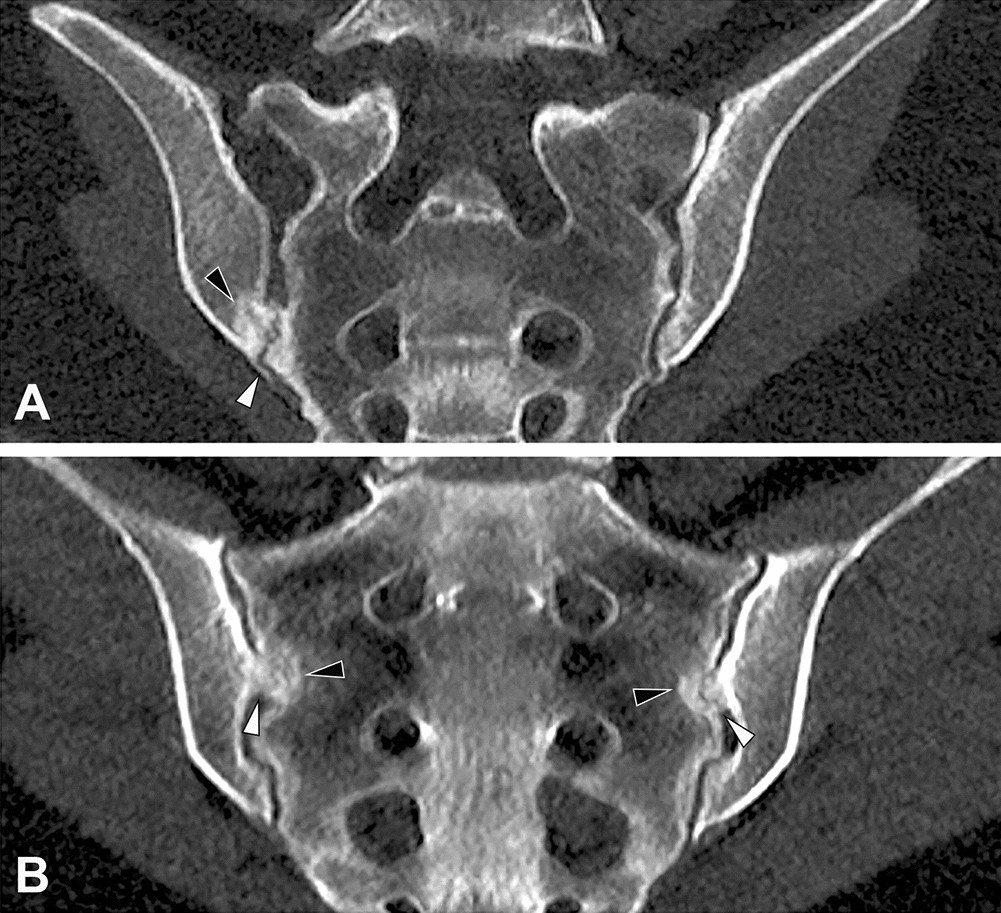

Figure 4

Imaging examples. (A) Female patient with bilateral accessory joints, paracoronal reconstruction. Note the accessory joint facet (white arrowhead) with associated periarticular sclerosis (black arrowhead). (B) Female patient with bilateral iliosacral complex, paracoronal reconstruction. Note the convex ilium notches (white arrowheads), again with associated periarticular sclerosis (black arrowheads).